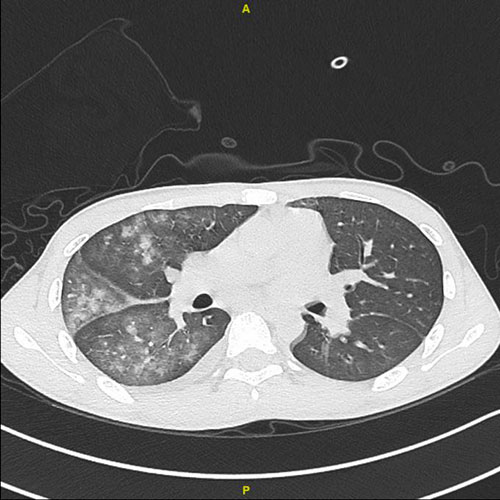

(胸部CT显示双肺见大面积的云雾状密度增高影,考虑双侧肺水肿。)

3月初的一天,在金湾区某大学就读的大一学生小严 (化名)因为咳嗽和气促来到了省医珠海医院诊治。小严热爱运动,身体一直都不错,以为只是普通感冒咳嗽,没想到当天夜里就被宣告病危: 气道出现大量粉红色泡沫痰,ct提示双肺严重感染, 心肺功能急剧下降,多器官功能出现障碍, 无创呼吸机已无法维持呼吸,需要气管插管机械通气……